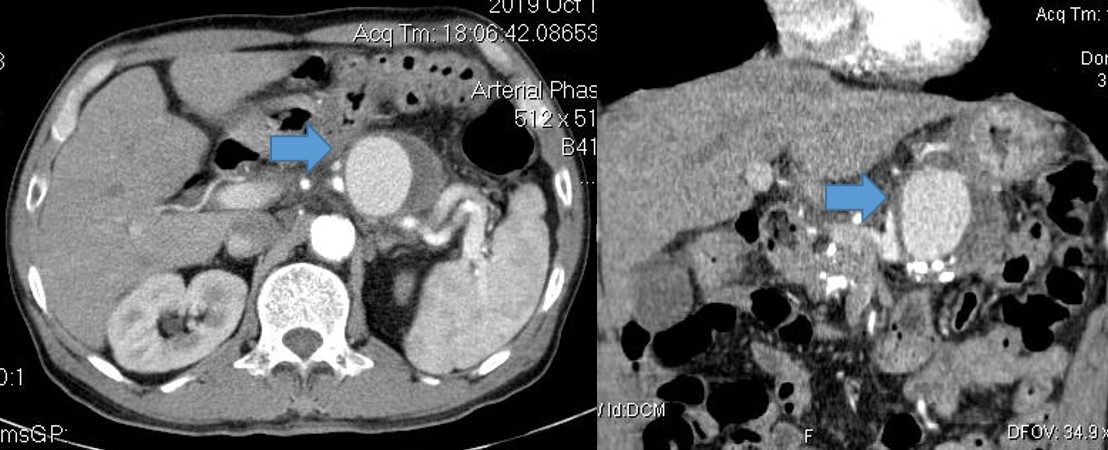

Bệnh nhân được truyền máu 4 đơn vị máu và nội soi dạ dày cấp cứu, ghi nhận hình ảnh máu tươi phun ra từ lỗ nhú tá lớn. Chẩn đoán ban đầu là chảy máu từ đường mật hoặc tụy. Bệnh nhân được siêu âm và chụp cắt lớp vi tính (CLVT). Phim chụp CLVT cho thấy hình ảnh một túi giả phình động mạch lách kích thước lớn gần gốc động mạch lách, bên trong có huyết khối. Nhu mô tụy teo mỏng và vôi hóa nhiều, hình ảnh điển hình của viêm tụy mạn. Sau khi hội chẩn đa chuyên khoa gồm Nội soi tiêu hóa, Nội tổng hợp, Chẩn đoán hình ảnh, Ngoại tiêu hóa, đơn vị DSA, Gây mê hồi sức, bệnh nhân được chẩn đoán là chảy máu cấp nặng từ ống tụy chính do vỡ túi giả phình động mạch lách trên nền viêm tụy mạn.

Hình 2. Túi giả phình kích thước lớn ở động mạch lách (mũi tên xanh)/ viêm tụy mạn.